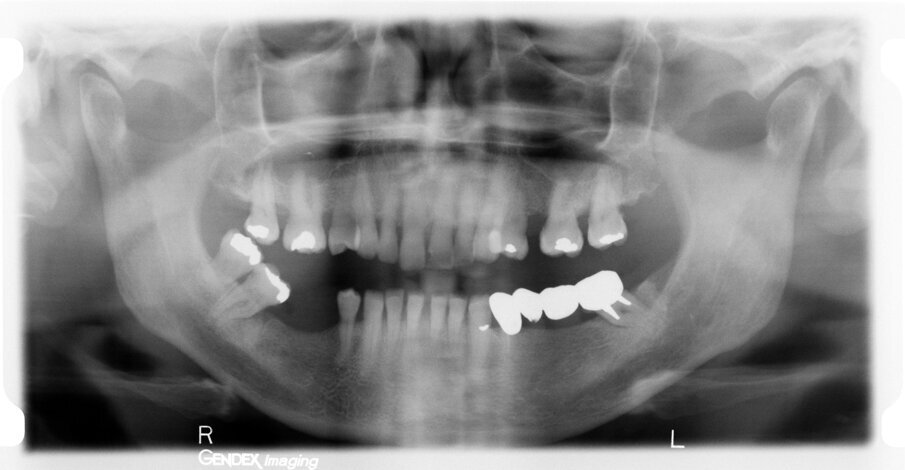

After three years, a panoramic radiograph was performed, highlighting excellent maintenance of the bone trophism and closure of the osteotomies created with the insertion of the implants (Fig. 5). Results of this type testify to the ideal biomechanical situation created above the implants, which are then protected from any bacterial infiltration, not only by the mucosa, which appeared stable and healthy, but also by the bone bridge created to protect the implant necks.

A further radiographic check was carried out seven years after the implants had been placed and showed growth of the bone level and the formation of a curved bone profile to support the interdental papillae, which is typical of natural teeth (Figs. 6a &b). Caries occurred under the crown of tooth #37, but the patient did not wish to have it treated. Upon physical examination, the soft tissue appeared stable and of excellent trophism.